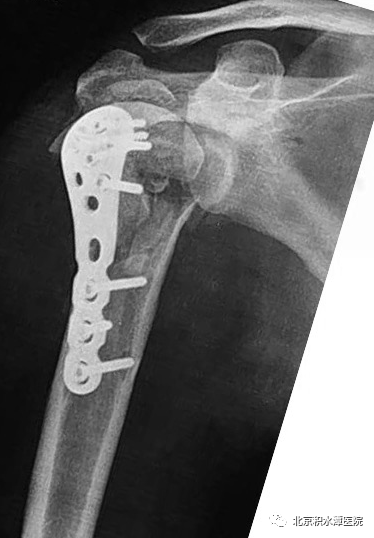

术后患者复查CT,见肩胛盂骨性重建良好。但为解决现有假体长度不足的问题,此次术后,蒋协远教授、黄强主任医师就带领团队医生与工程师团队进行了反复沟通,开始设计并定制合适的反肩假体。按健侧长度计算,肱骨近端骨缺损约8厘米,起初还在肿瘤型假体和APC方式间反复讨论,最后决定采用定制反肩假体结合异体骨(APC)的方式进行处理,同时还定制了相应长度的异体骨,以更好地恢复上肢长度和三角肌张力。

2022年8月18日,患者再次回到北京积水潭医院,蒋协远教授带领黄强主任医师和查晔军副主任医师、公茂琪主任医师等为患者进行了APC反肩置换手术治疗。术中见肩胛盂骨性结构重建良好,取出螺钉,顺利安装肩盂侧反球假体。并反复通过测量和软组织张力判断,确定了异体骨长度,安装肱骨侧假体后,以异体骨板捆扎保护,手术过程顺利,拍片见肩关节假体位置满意。